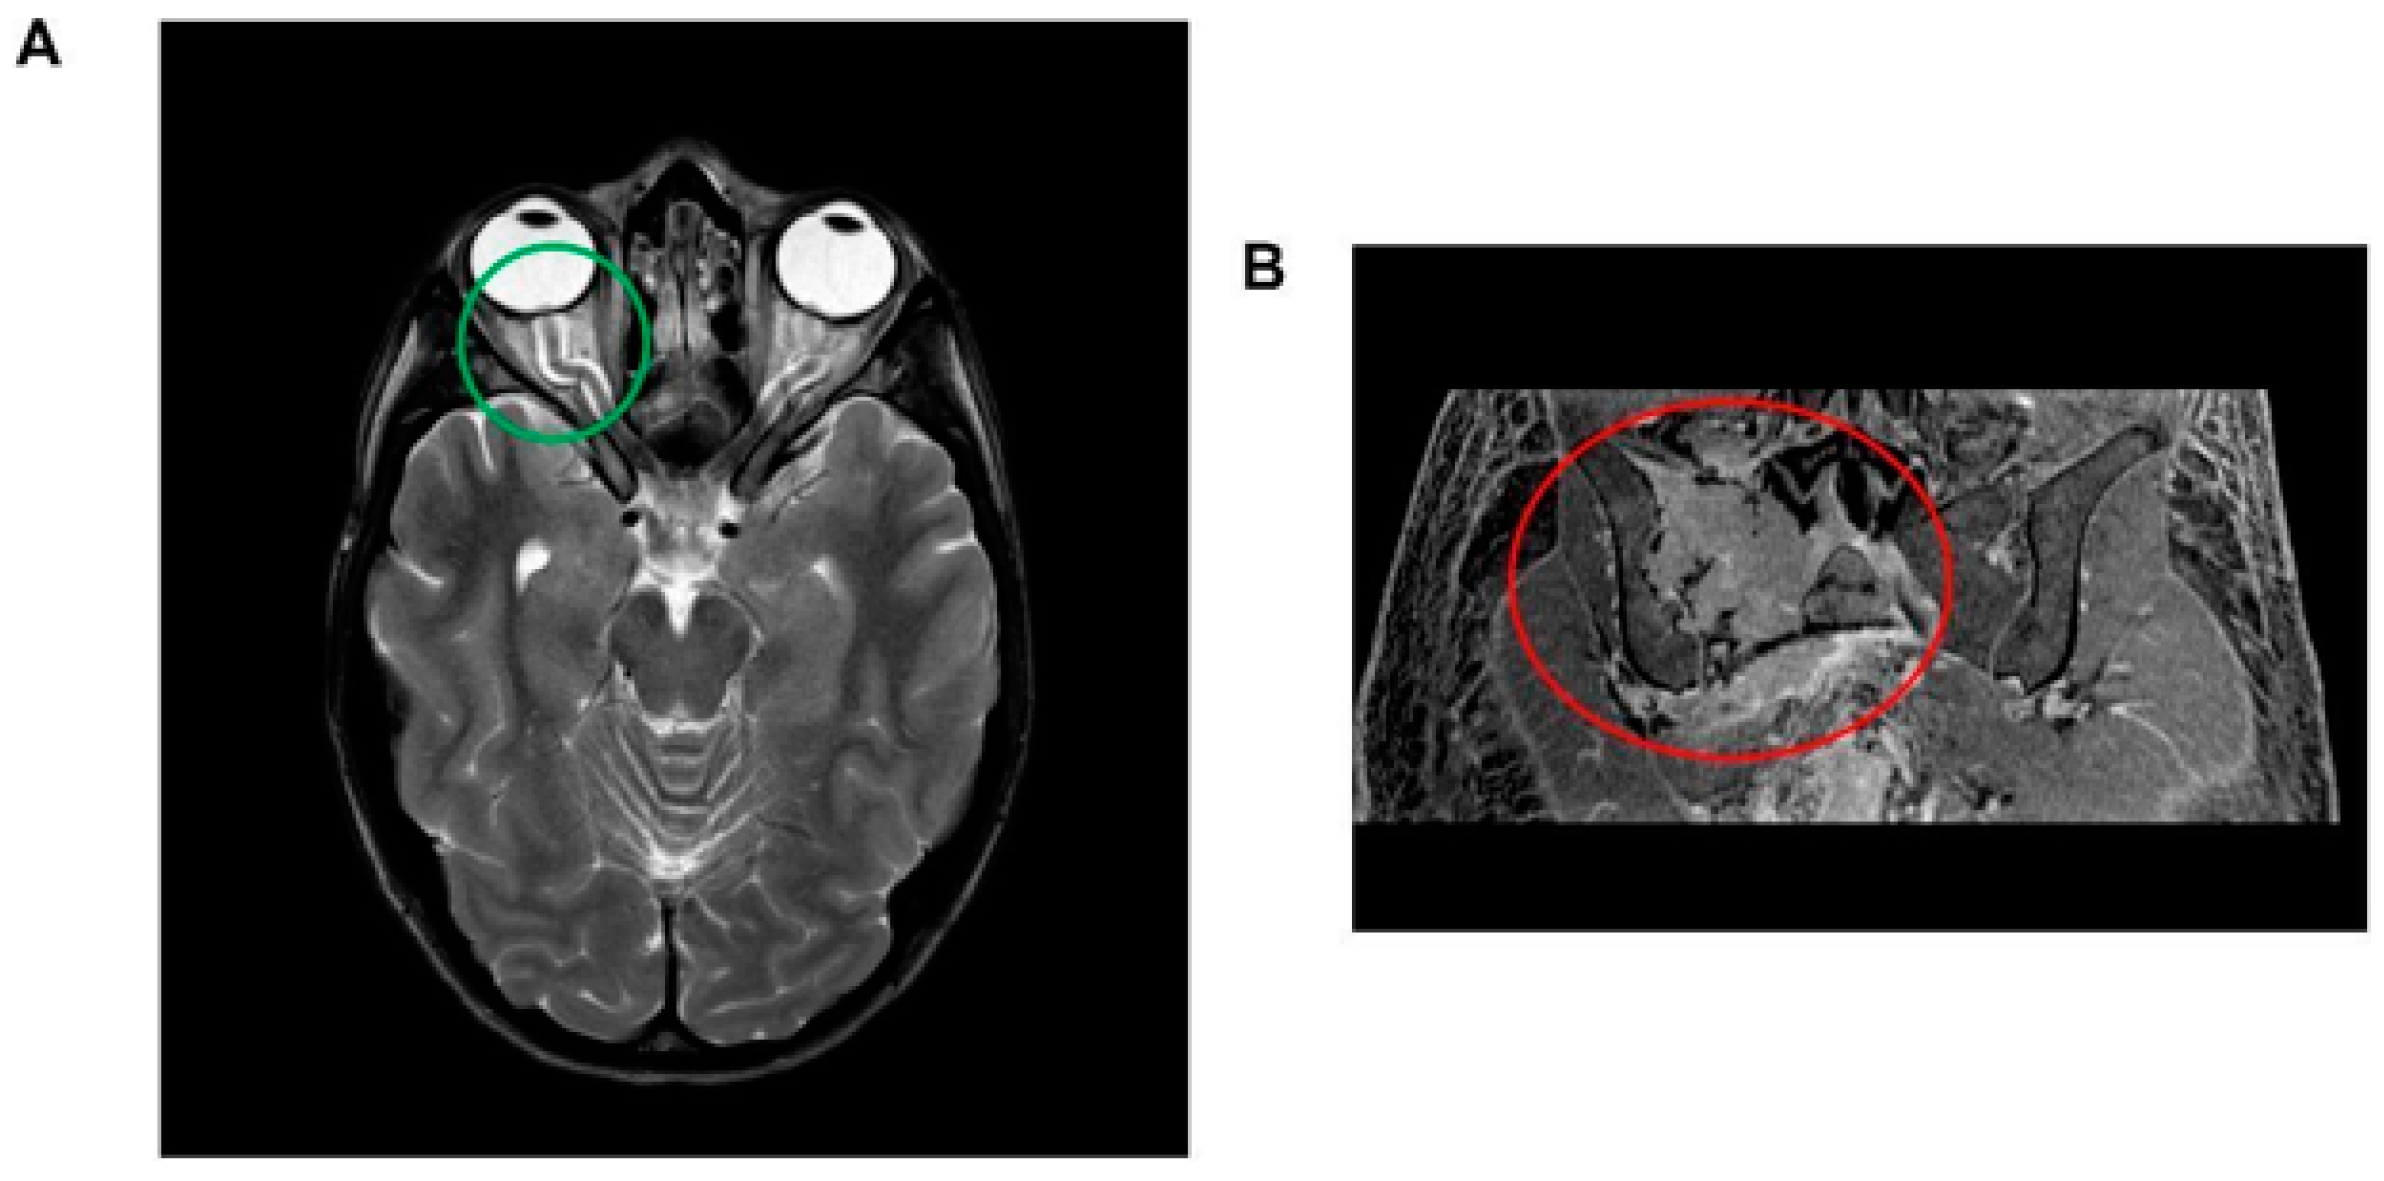

Brain magnetic resonance imaging (MRI) revealed indirect signs of intracranial hypertension, including optic nerve tortuosity with sheath enlargement and intraocular protrusion of the optic nerve head, along with flattening of the posterior sclera. Significant enhancement of the optic disc was also observed (Figure 1A). Angio-MRI findings revealed distinct constriction in the dural venous sinuses around the transverse and sigmoid sinus junctions, which is a trait observed in approximately 90% of individuals with suspected idiopathic intracranial hypertension. Other potential causes—such as secondary intracranial hypertension, venous sinus thrombosis, and parenchymal lesions—were carefully excluded. Fundoscopic examination confirmed bilateral papilledema.

Figure 1.

(A) Brain magnetic resonance imaging (MRI) illustrating indirect indicators of intracranial hypertension. Notable features include the tortuosity of the optic nerve accompanied by sheath enlargement and the intraocular protrusion of the optic nerve head, which is coupled with posterior scleral flattening (highlighted within the green circle). Additionally, a significant enhancement of the optic disc is observed. (B) Abdominal magnetic resonance imaging (MRI) depiction of a lesion located at the right hip, exhibiting transverse diameters of 70 × 66 mm. The lesion is characterized by a composition of both osteolytic and osteosclerotic components (encircled in red).